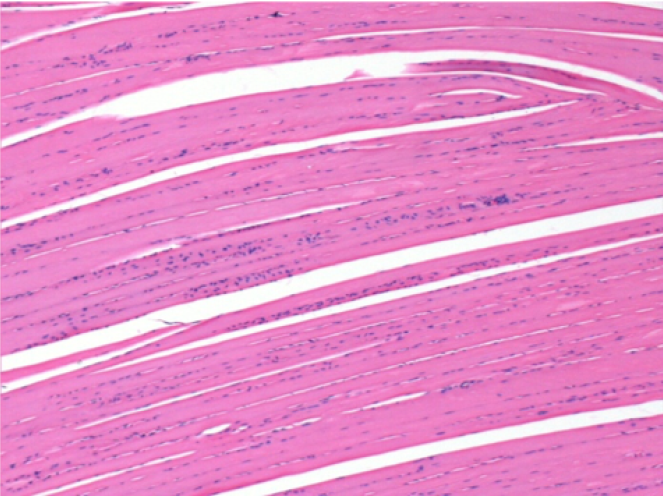

7 meses (D210) después de la inyección IM de Endopeel 0,1 ml en el músculo pretibial derecho.

Restitutio ad integrum (restauración a la condición original) completa después de 7 meses

L :Control 50xD210

R50X-D210